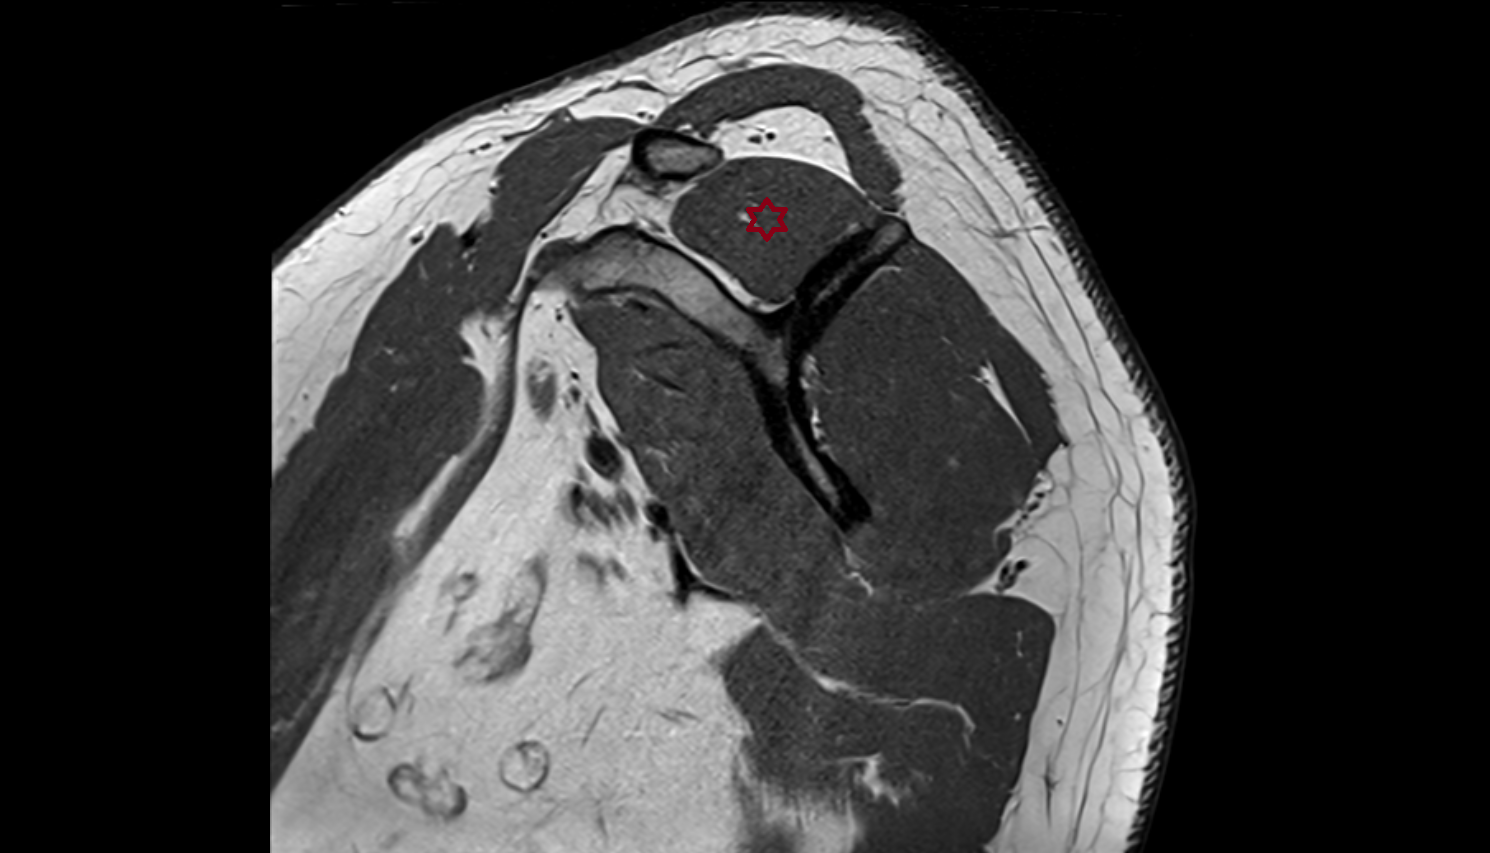

- Shoulder joint (glenohumeral joint)

- Glenoid labrum

- Supraspinatus tendon

- Subacromial space